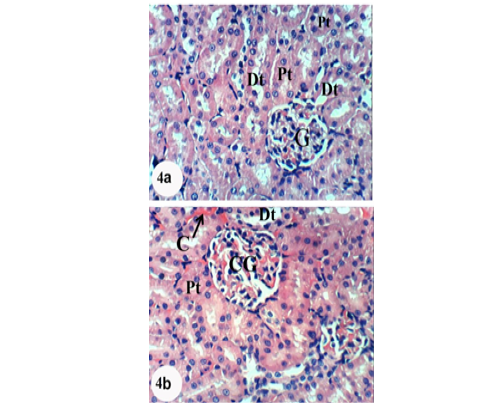

Photomicrographs of H&E stained kidney sections of APAP-administered rats treated with naringenin showing normal structure of kidney; normal glomerulus, proximal and distal tubules. Slight glomerular and intertubular congestion was observed in 4b. X400